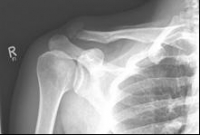

Images: A lateral clavicle fracture was treated with a hook plate. The hook is fixed under the acromioclavicular, while screws anchor the plate in the collarbone.